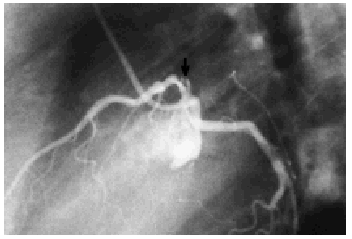

Se practicó un cateterismo cardíaco y una coronariografía, que revelaron una disección del segmento proximal de la arteria descendente anterior que involucraba el ostium de esta arteria y el segmento más distal del tronco, con un flujo distal TIMI III (fig. 2). El resto de los vasos coronarios no presentaban lesiones de ningún tipo. Se decidió finalmente revascularizar dicha arteria mediante un injerto de arteria mamaria interna. La evolución de la paciente fue satisfactoria, permaneciendo asintomática 6 meses después de su revascularización.

Figura 2. Coronariografía izquierda en una proyección lateral que muestra una imagen sugestiva de disección en el segmento proximal de la arteria descendente anterior.